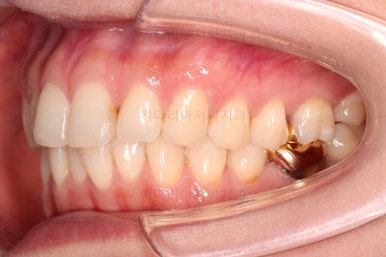

마찬가지로 부산치아교정비용 초진 시 입안의 모습입니다.

아랫니가 많이 보이지 않는 타입이라서 잘 몰랐는데 입안을 관찰해 보니 아래 앞니가 삐뚤어 있네요.

이 부분도 꼭 교정해야 될 정도는 아니여서 선택의 문제라고 할 수 있는데요.

어금니가 문제였습니다.

윗니 어금니가 하나 없는 상태였고요.

어금니가 없이 지낸지 꽤 시간이 흐른터라 뒤쪽 어금니가 앞으로 쓰러져 공간을 잠식하고 있었습니다.